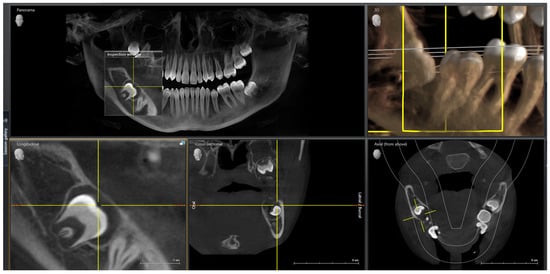

1. Introduction

2.1. Diagnosis and Etiology

2.2. Treatment Objectives